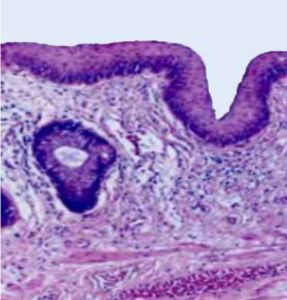

External Anal Margin

histology-external-anal-margin

• keratinized

• thick 90-100 um

• dry

• resistant

Perianal Area

histology-perianal-area

• non-keratinized

• thin 60-75 um

• moist

• highly sensitiv

• transition zone